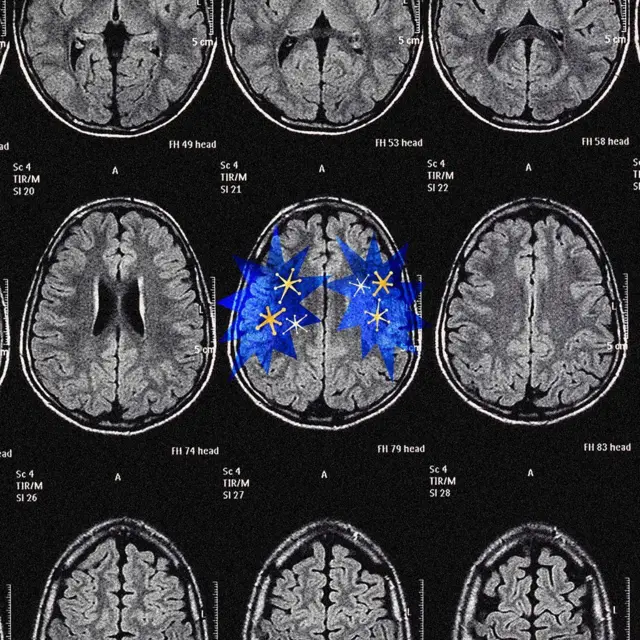

Para entender por qué, necesitamos analizar cómo dos partes de nuestro cerebro —la corteza cerebral y el sistema de recompensa, incluida la dopamina— nos impulsan en diferentes direcciones.

Fuente de la imagen, Serenity Strull. Estudios realizados en ratas indican que la liberación de dopamina se relaciona más con la sorpresa que con la obtención de la recompensa en sí.

Fuente de la imagen, Serenity Strull. Podría ser más acertado considerar la dopamina como una señal imperativa que nos indica que debemos «resolver esto», aunque se necesita más investigación para confirmarlo.